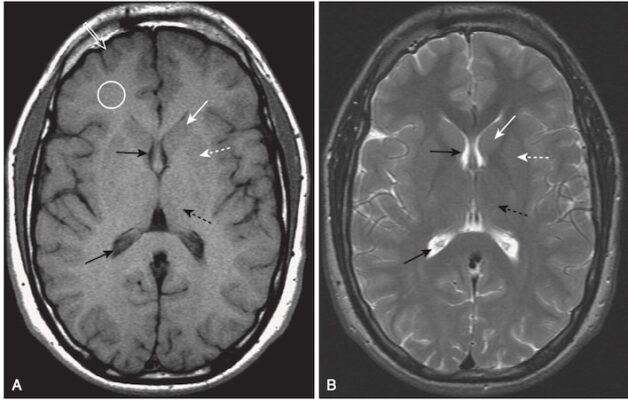

- Phát hiện thường gặp nhất là nhiều vùng sáng trên ảnh T2W tại điểm nối vỏ-tuỷ ở thuỳ thái dương hoặc thuỳ đỉnh hoặc trong thể chai (Hình 13).